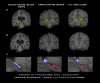

Preterm newborns with germinal matrix-intraventricular hemorrhage (GM-IVH) are at a higher risk of evidencing neurodevelopmental alterations. Present study aimed to explore the long-term effects that GM-IVH have on hippocampal subfields, and their correlates with memory. The sample consisted of 58 participants, including 36 preterm-born (16 with GM-IVH and 20 without neonatal brain injury), and 22 full-term children aged between 6 and 15 years old. All participants underwent a cognitive assessment and magnetic resonance imaging study. GM-IVH children evidenced lower scores in Full Intelligence Quotient and memory measures compared to their low-risk preterm and full-term peers. High-risk preterm children with GM-IVH evidenced significantly lower total hippocampal volumes bilaterally and hippocampal subfield volumes compared to both low-risk preterm and full-term groups. Finally, significant positive correlations between memory and hippocampal subfield volumes were only found in preterm participants together; memory and the right CA-field correlation remained significant after Bonferroni correction was applied (p = .002). In conclusion, memory alterations and both global and regional volumetric reductions in the hippocampus were found to be specifically related to a preterm sample with GM-IVH. Nevertheless, results also suggest that prematurity per se has a long-lasting impact on the association between the right CA-field volume and memory during childhood.